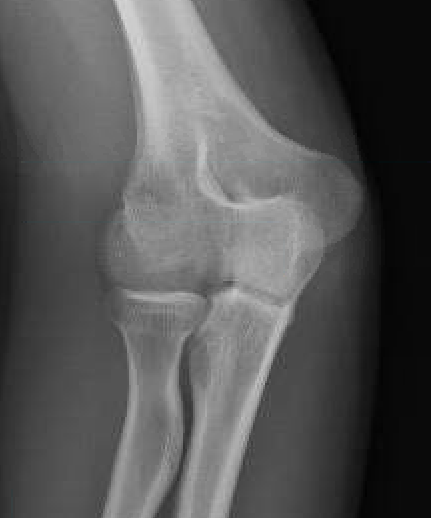

Capitellum fracture with radial head fracture

Concomitant injuries

Radial head

Watts et al JBJS Br 2007

- 79 capitellar fractures

- 24% had a radial head fracture as well